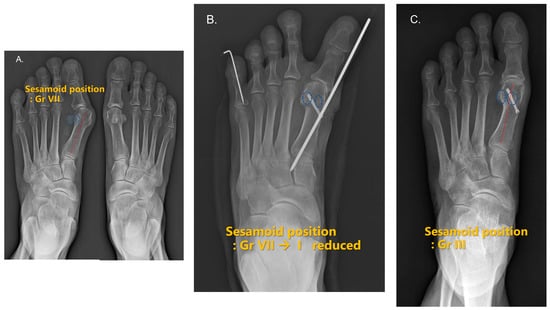

3.3. Medial Sesamoid Position

| DCMO (n = 30, 50%) | S.E.R.I. (n = 30, 50%) | |||||

| Grade | Pre-Operative | Early Follow-Up | Most Recent Follow-Up | Pre-Operative | Early Follow-Up | Most Recent Follow-Up |

| I | 3 (10%) | 1 (3%) | 16 (53%) | 7 (23%) | ||

| II | 10 (33%) | 5 (17%) | 4 (13%) | 3 (10%) | ||

| III | 9 (30%) | 6 (20%) | 5 (17%) | 8 (27%) | ||

| IV | 4 (13%) | 5 (17%) | 5 (17%) | 6 (20%) | ||

| V | 10 (33%) | 4 (13%) | 10 (33%) | 6 (20%) | 5 (17%) | |

| VI | 2 (7%) | 3 (10%) | 7 (23%) | 1 (3%) | ||

| VII | 18 (60%) | 17 (57%) | ||||

| DCMO (n = 30, 50%) | S.E.R.I. (n = 30, 50%) | p value | ||||

| Grade difference | ||||||

| Pre-op to early follow-up | −3.4 ± 1.1 | −4.4 ± 1.4 | 0.003 * | |||

| Pre-op to most recent follow-up | −2.4 ± 1.5 | −3.3 ± 1.7 | 0.028 * | |||

| Early to Most recent follow up | 1.0 ± 1.0 | 1.1 ± 1.2 | 0.822 * | |||

| Laterally displaced sesamoid | ||||||

| Pre-op | 30 (100%) | 30 (100%) | 0.999 † | |||

| Early follow-up | 4 (13%) | 0 (0%) | 0.038 † | |||

| Most recent follow-up | 13 (42%) | 6 (20%) | 0.052 † | |||